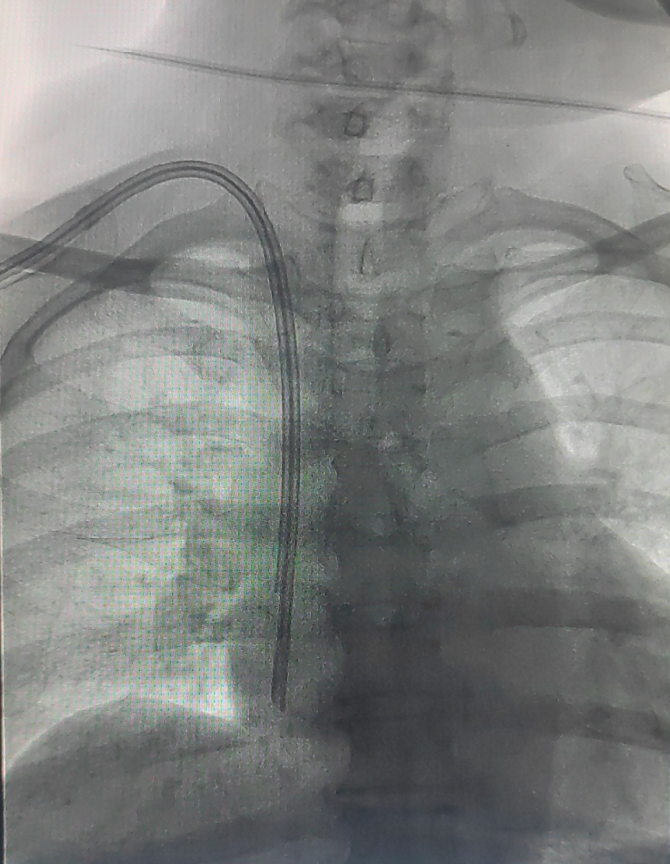

该患者由肾脏内科方敬爱教授医疗小组张紫媛、范彦君医生主管,诊断为尿毒症,行规律血液透析治疗,近期因心力衰竭、血压低等因素导致左侧自体动静脉内瘘堵塞,拟建立血管通路入院。经科室讨论后,本次手术在介入科DSA手术室进行,在实时透视引导下,清晰辨识患者右颈内静脉路径,一次性成功穿刺并将导丝送入下腔静脉。随后,建立皮下隧道,将带涤纶套的透析导管尖端精准定位至右心房中上部。术中全程严格无菌操作,患者生命体征平稳,术后无出血、感染、血气胸等并发症,次日透析时导管血流量充足,达到预期治疗效果。

对于部分血管资源耗竭、心功能差、中心静脉狭窄或闭塞,以及需等待内瘘成熟的透析患者,TCC是重要的半永久血管通路。虽然传统盲穿或超声引导置管已广泛应用,但在极端血管变异、严重中心静脉病变等复杂情况下,仍存在置管失败、导管异位、血流不畅等问题。DSA引导下置管技术,利用DSA实时高清成像,可全程可视化显示血管形态、走行及病变情况,实现导丝、导管的精准定位与放置。该技术的核心优势在于:在DSA直接透视下操作,能有效避免误穿与误入,精准将导管尖端置于理想位置(如右心房中上部),同时实时影像监测有助于显著降低血管损伤、血肿、气胸及心律失常等并发症风险,尤其适用于既往多次置管、肥胖、解剖变异及中心静脉狭窄/闭塞的疑难病例,可根据患者血管条件灵活调整入路与导管位置,实现“一人一策”。